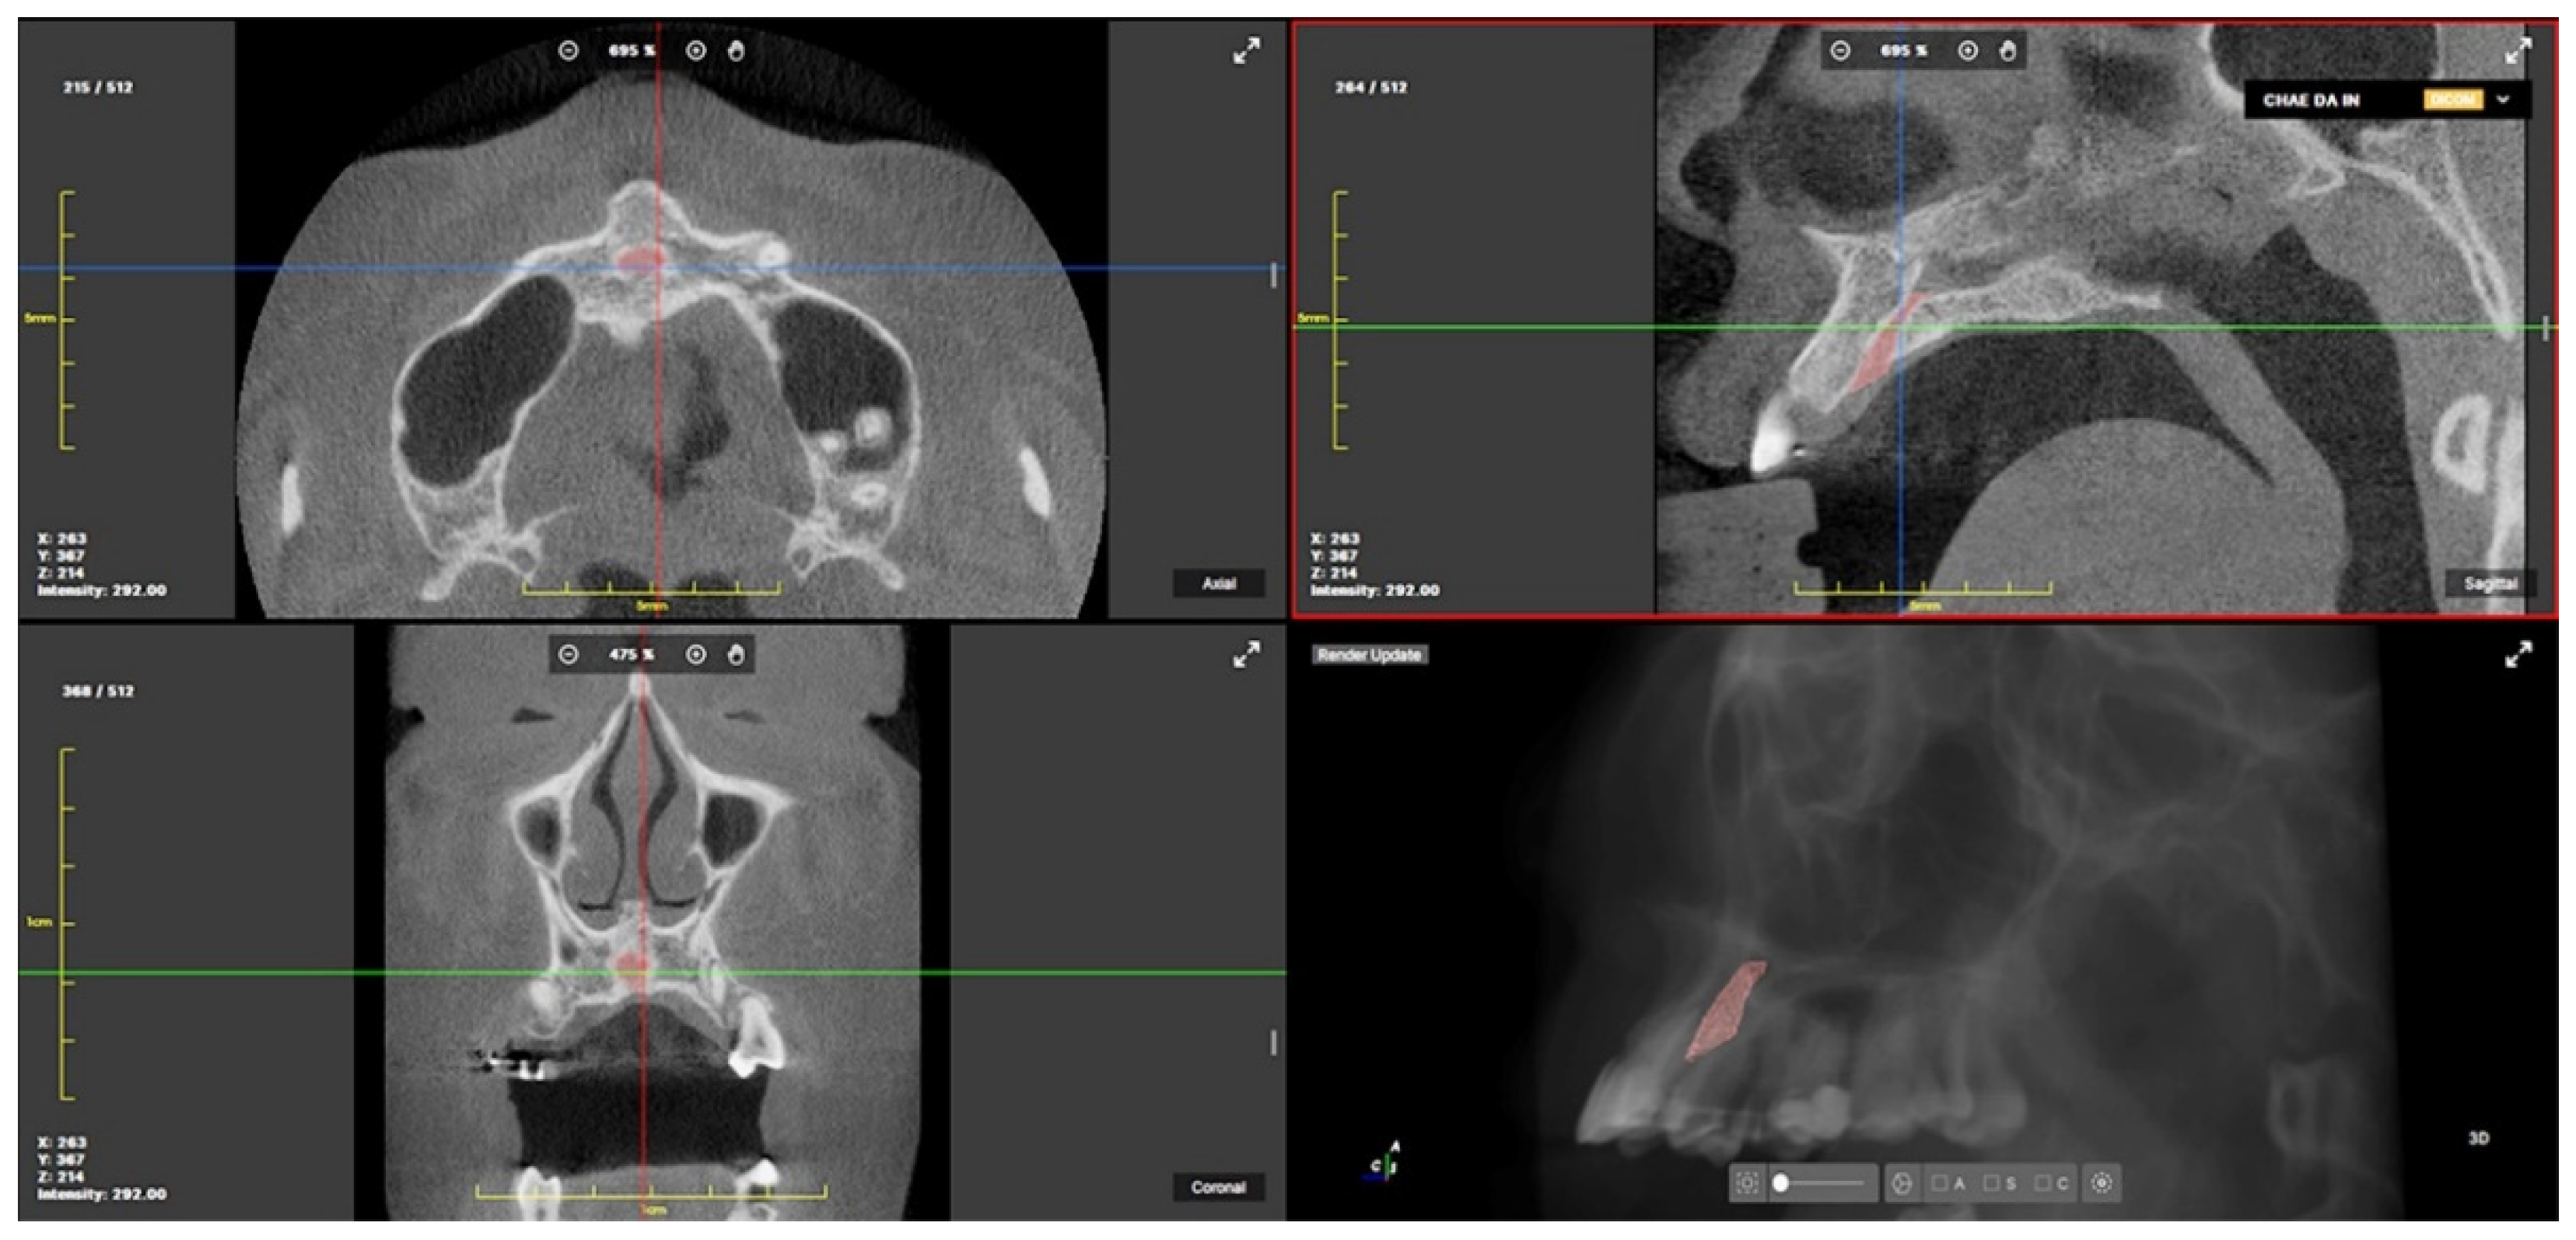

2.3. CBCT Landmarks, Reference Planes and Measurements